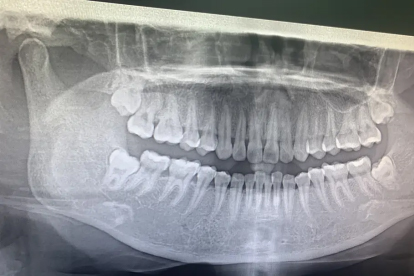

智齿拔出后牙齿整体后移属于异常现象,通常与拔牙后邻牙移位或咬合关系改变有关。智齿拔除后可能出现邻牙倾斜、对颌牙伸长或牙弓形态改变,需通过正畸干预或修复治疗恢复咬合功能。

智齿拔除后牙列后移多因拔牙间隙未得到有效维持。当第三磨牙缺失时,第二磨牙可能向远中方向倾斜,尤其在下颌更为常见。这种移位在拔牙后3-6个月内进展较快,与牙周膜改建、舌体压力及咀嚼习惯改变相关。临床表现为前牙区出现散在间隙、后牙区咬合接触面积减少,可能伴随颞下颌关节不适。早期可通过佩戴保持器或片段弓矫治器控制移位程度。

少数情况下牙齿后移涉及复杂力学改变。当存在多颗牙缺失或牙周支持组织薄弱时,可能引发全牙列适应性移位,常见于长期未修复的游离端缺失病例。这类患者往往伴有牙槽骨吸收、咬合垂直距离降低,需通过咬合重建或种植修复恢复颌位关系。对于伴有颞下颌关节紊乱症状者,还需配合颌垫治疗调整髁突位置。